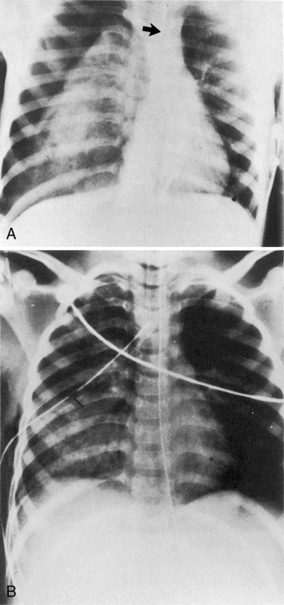

Spinal cord injuries are less common in children than in adults. When these injuries occur in children, they are generally associated with motor vehicle-related crashes, falls, and inflicted head trauma and can result in injuries of the upper or lower cervical spine (Fig. 19-1).4

Fig. 19-1 Cervical spine injury. Lateral cervical spine radiograph indicating cervical spine injury. A, Cervical spine radiograph of a toddler demonstrating wide separation between the first and second cervical vertebrae, consistent with complete cervical spine injury at the level of C1 to C2. Note the anterior displacement of the nasogastric tube (arrow) indicating anterior displacement of the esophagus (which should lie just anterior to the vertebrae) caused by edema at the site of the spinal cord injury. This child was intubated, but the endotracheal tube is not visible because it is not radiopaque. B, Normal anatomy of the cervical spine in a toddler. Note the horizontal articulation of the vertebrae, which increases the mobility of the upper cervical spine in this age group.

(A. Radiograph courtesy of John B. Pietsch, Nashville, TN. B. Illustration from Riviello JJ, et al: Delayed cervical central cord syndrome after trivial trauma. Pediatr Emerg Care 6:116, 1990. Williams and Wilkins.)